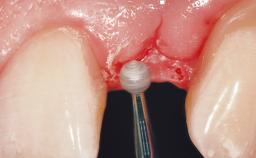

Immediate Flapless Placement of an Implant in a Maxillary Left Central Incisor Site

Placement Protocol Immediate implant placement

Tooth Site Maxillary incisor or canine

Socket Morphology Single-root socket

Socket Integrity Damage to one or more bone walls